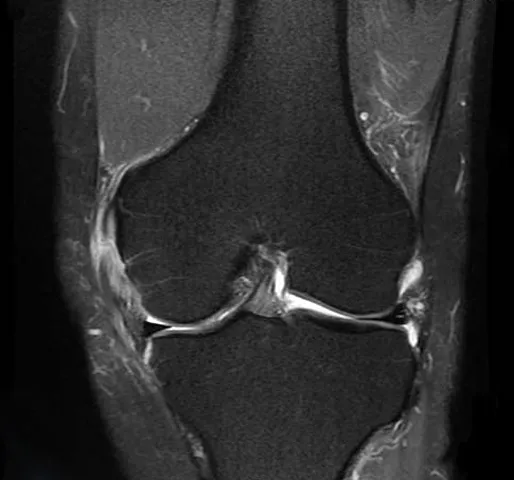

두 번째는 연골 손상

무릎 관절 사이에서 뼈와 뼈의 마찰을 줄여주는 부드러운 조직인 연골이 관련되어 있습니다. 나이 증가, 과체중, 관절염 등으로 인해 연골이 닳거나 소실되면, 뼈 사이의 직접적인 마찰로 인해 통증이 발생할 수 있으며, 이로 인해 움직임의 제한, 삐걱거리는 소리, 염증과 같은 증상이 나타날 수 있습니다.

이 상태의 치료는 체중 감량, 적절한 운동, 보조기 사용과 같은 자가 관리와 필요에 따라 진통제, 항염제, 보호주사, 관절경 수술 등의 의학적 치료를 포함할 수 있습니다.